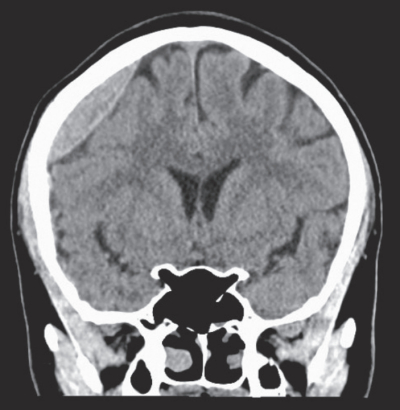

47歳の男性。職場の飲み会の帰りに歩道橋の階段を踏みはずして受傷し、救急車で搬入された。

来院時の意識レベルはJCS II-10。体温 36.6 ℃。血圧 126/88 mmHg。心拍数 80/分、整。呼吸数 16/分。SpO2 99%(リザーバー付マスク10L/分 酸素投与下)。来院時に緊急で撮影された頭部単純CTの水平断像と冠状断像および骨条件の水平断像と冠状断像を別に示す。

診断はどれか。2つ選べ。

a. 頭蓋骨骨折

b. 急性硬膜外血腫

c. 急性硬膜下血腫

d. 外傷性脳内血腫

e. びまん性軸索損傷